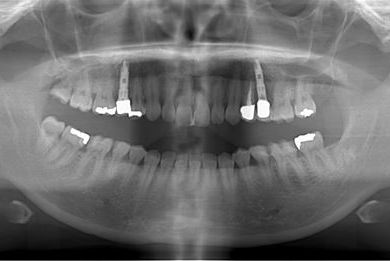

インプラントの症例写真 IMPLANT

| 治療内容 | インプラント2本(ソケットリフト、抜歯即日スピードインプラント)、メタルボンドセラミッククラウン3本(メタルボンドセラミック用土台1本)、ハイブリッドセラミックインレー4本 | ||||||||||||||||||||||||||||||||

| 治療期間 | 10ヶ月 |

治療前